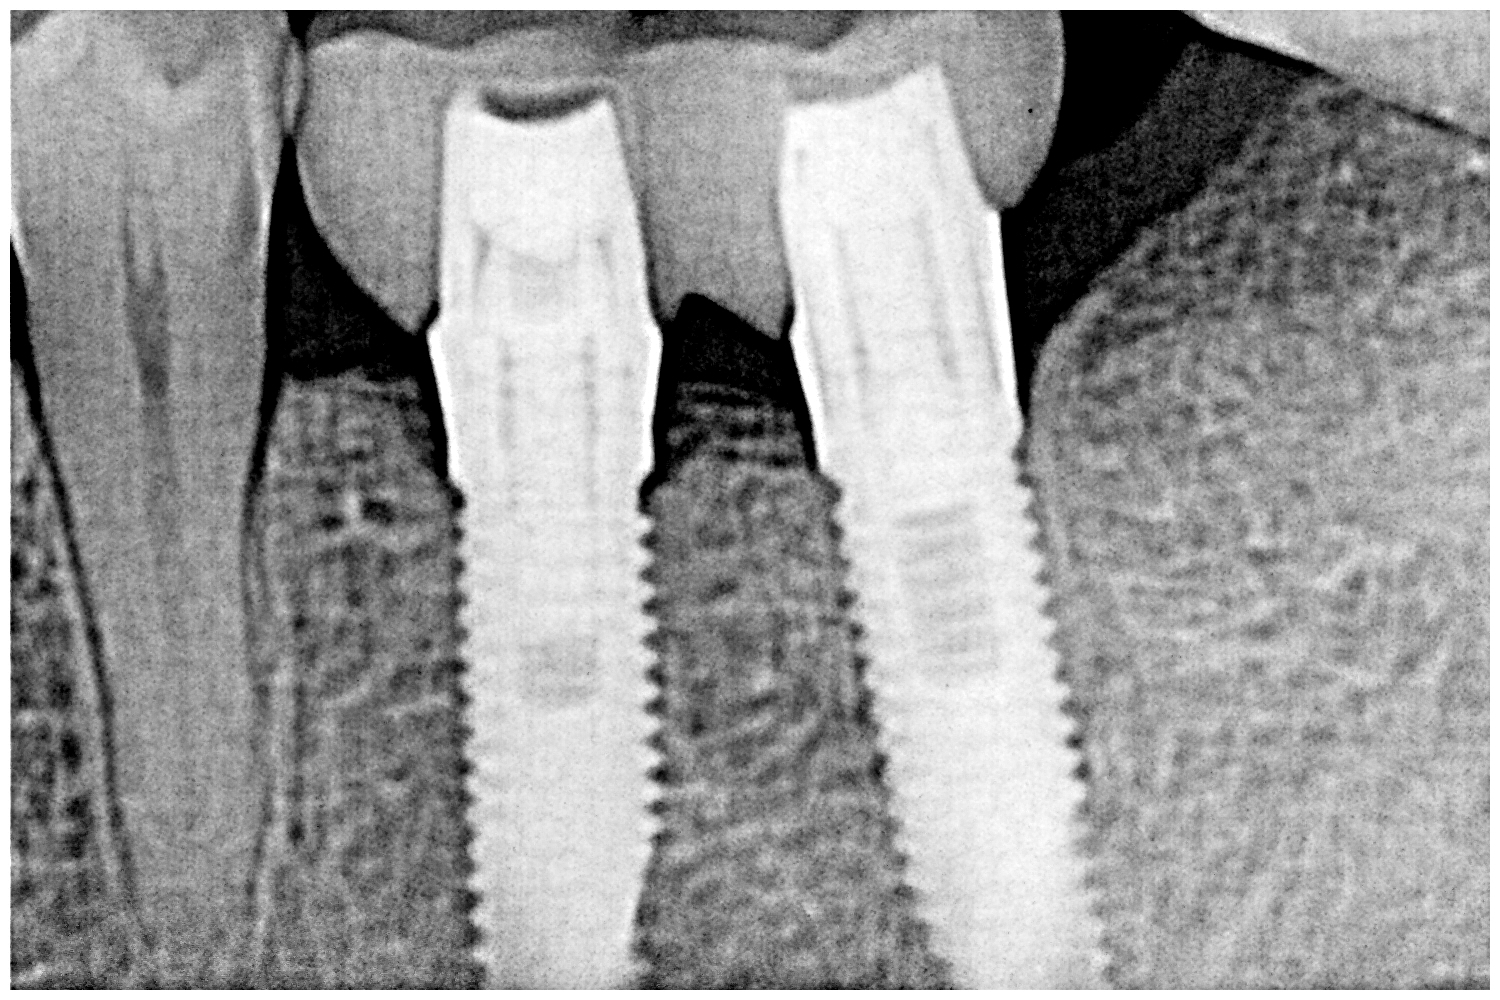

デンタルとパノラマになります

4mmの13mmというインプラントを埋入しています

綺麗に仕上がりました